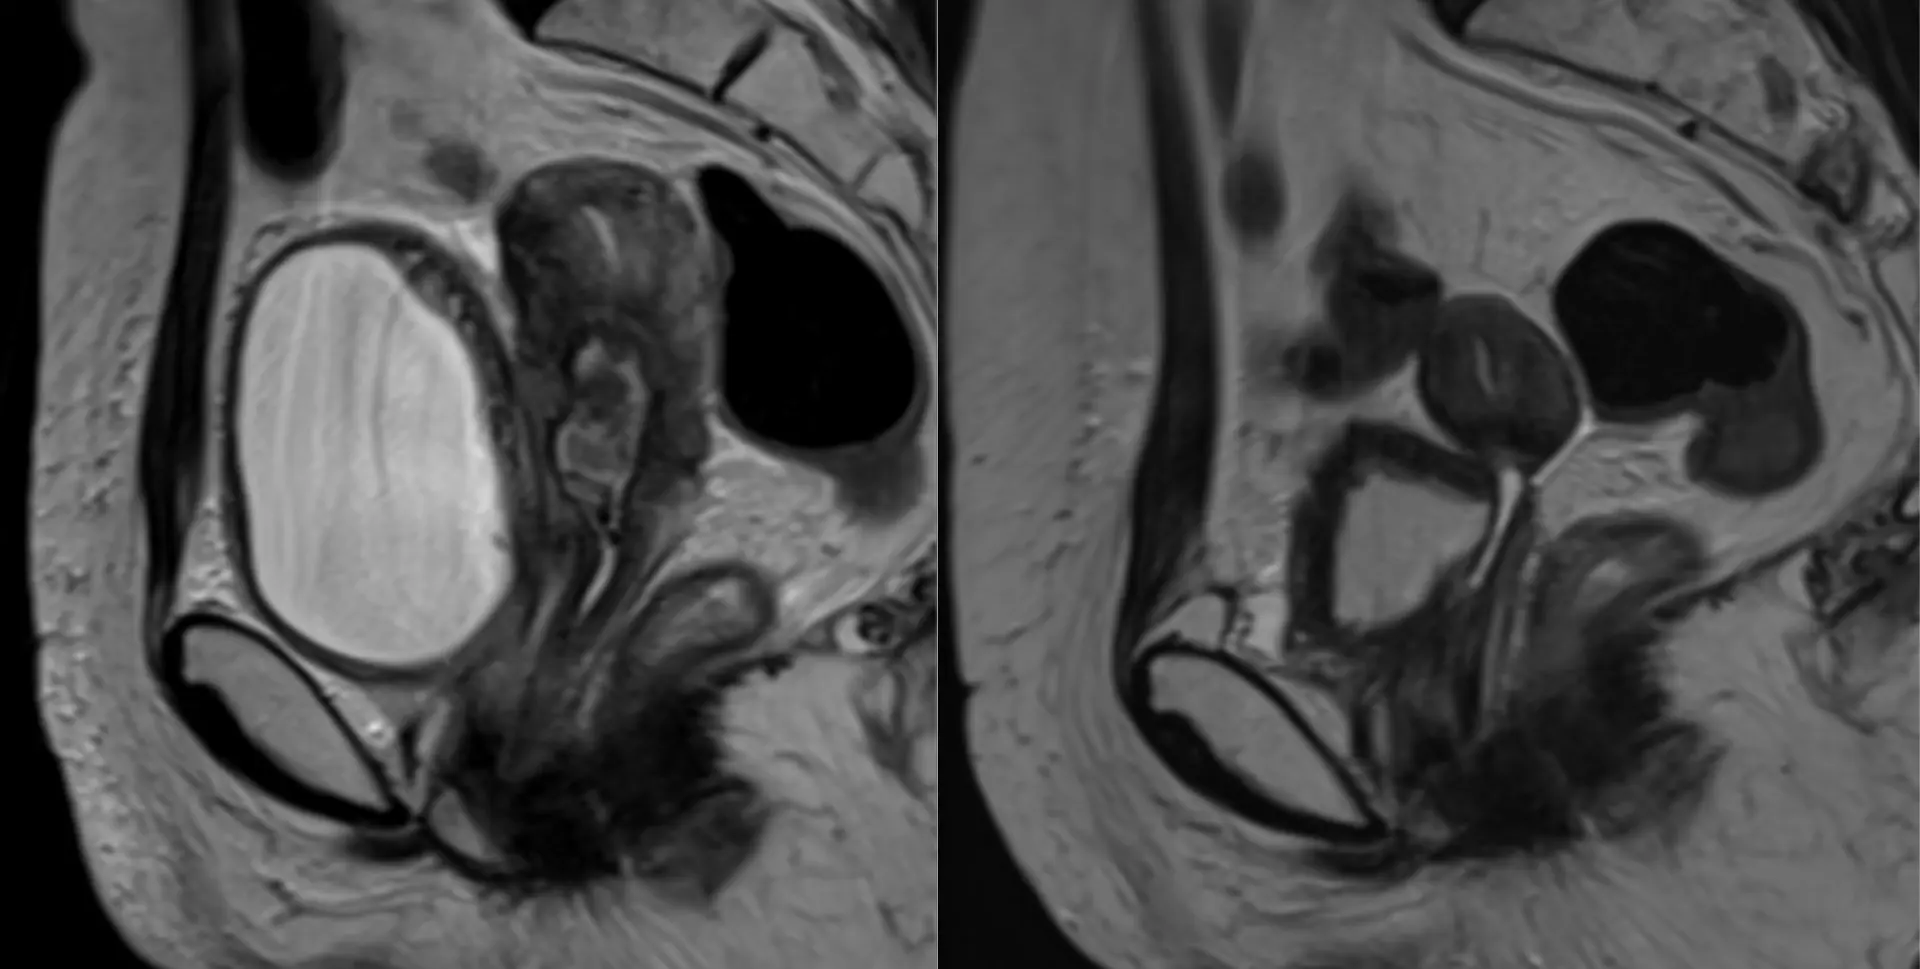

Вот такие плечики у пациента 29 лет! Во время эпидемии COVIDa-19 перенёс тяжёлую форму, лечили, в том числе, высокими дозами кортикостероидов, так что остеонекроз, который мы имеем возможность видеть в головках плечевых костей, по всей видимости, развился, как осложнение этого вида терапии. Хотя, при этой инфекции возникает ещё и гиперкоагуляция, которая и сама по себе является фактором риска развития некроза костей. В литературе такие случаи описаны и известны, есть описания развития остеонекроза даже четырёх костей одновременно (головок бедренных и плечевых костей), причём, развился он аж через полгода после окончания терапии. В нашем случае справа некроз привед к фрагментации головки плеча. Понятное дело, что функции плечевых суставов нарушены, в том числе, за счёт развития грубого вторичного артроза. Видимо, тотальная артропластика потребуется...